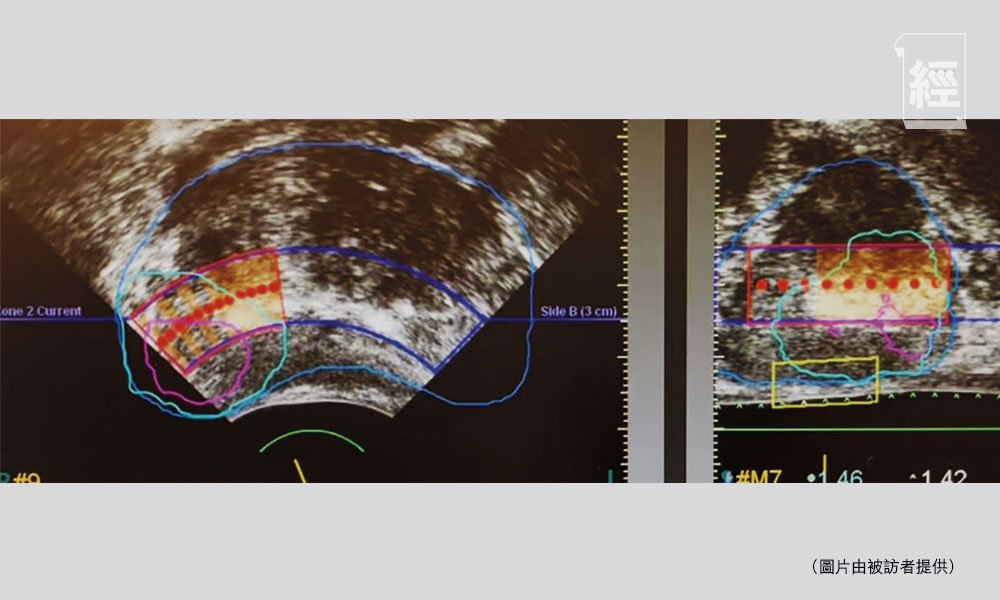

除了根治性切除,另一個新興方案是局部定位治療(Focal Therapy)。這種療法透過能量,如高強度聚焦超聲(HIFU)、微波消融術(Targeted Microwave Ablation, TMA)或冷凍治療(Cryotherapy),直接消滅癌細胞。

以高強度聚焦超聲(HIFU)為例,利用聚焦的超聲波能量產生約70至80°C的高溫,逐點燒毀癌細胞。治療時,超聲波能量是精準聚焦在術前已鎖定的腫瘤區域,只有焦點位置會產生高溫,而超聲波經過的路徑並不會加熱,因而避免了對直腸和周邊腸道造成損害。這項技術屬於非侵入性治療,病人恢復快。